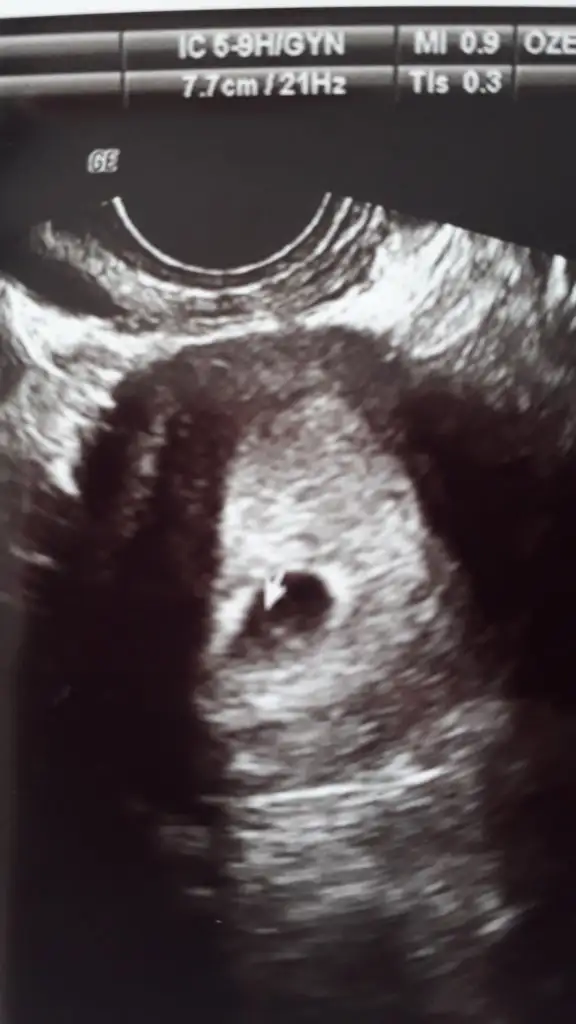

Keseyi gördük ve ne boş ne de dış gebelik olmadığını gayet saglıklı olduğunu geç döllenme olduğu için 5h 5g lük olduğunu haftaya da kalp atışlarını duyabileceğimizi söyledi. Çok mutluyum böylesonuçlanması çok mutlu etti beni allahım isteyen herkese nasip etsin inşallah. Burada bana destek olan rahatlatan herkese çok teşekkür ederim allah hepinizin gönlüne göre versin 🙏🙏❤❤🤗🤗🤗😍😍